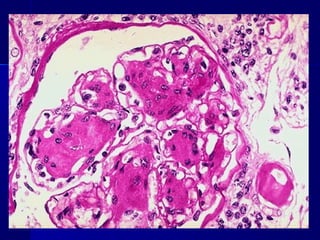

Insulitis en Diabetes Mellitus tipo 1

Insulitis en DiabetesMellitus tipo 1